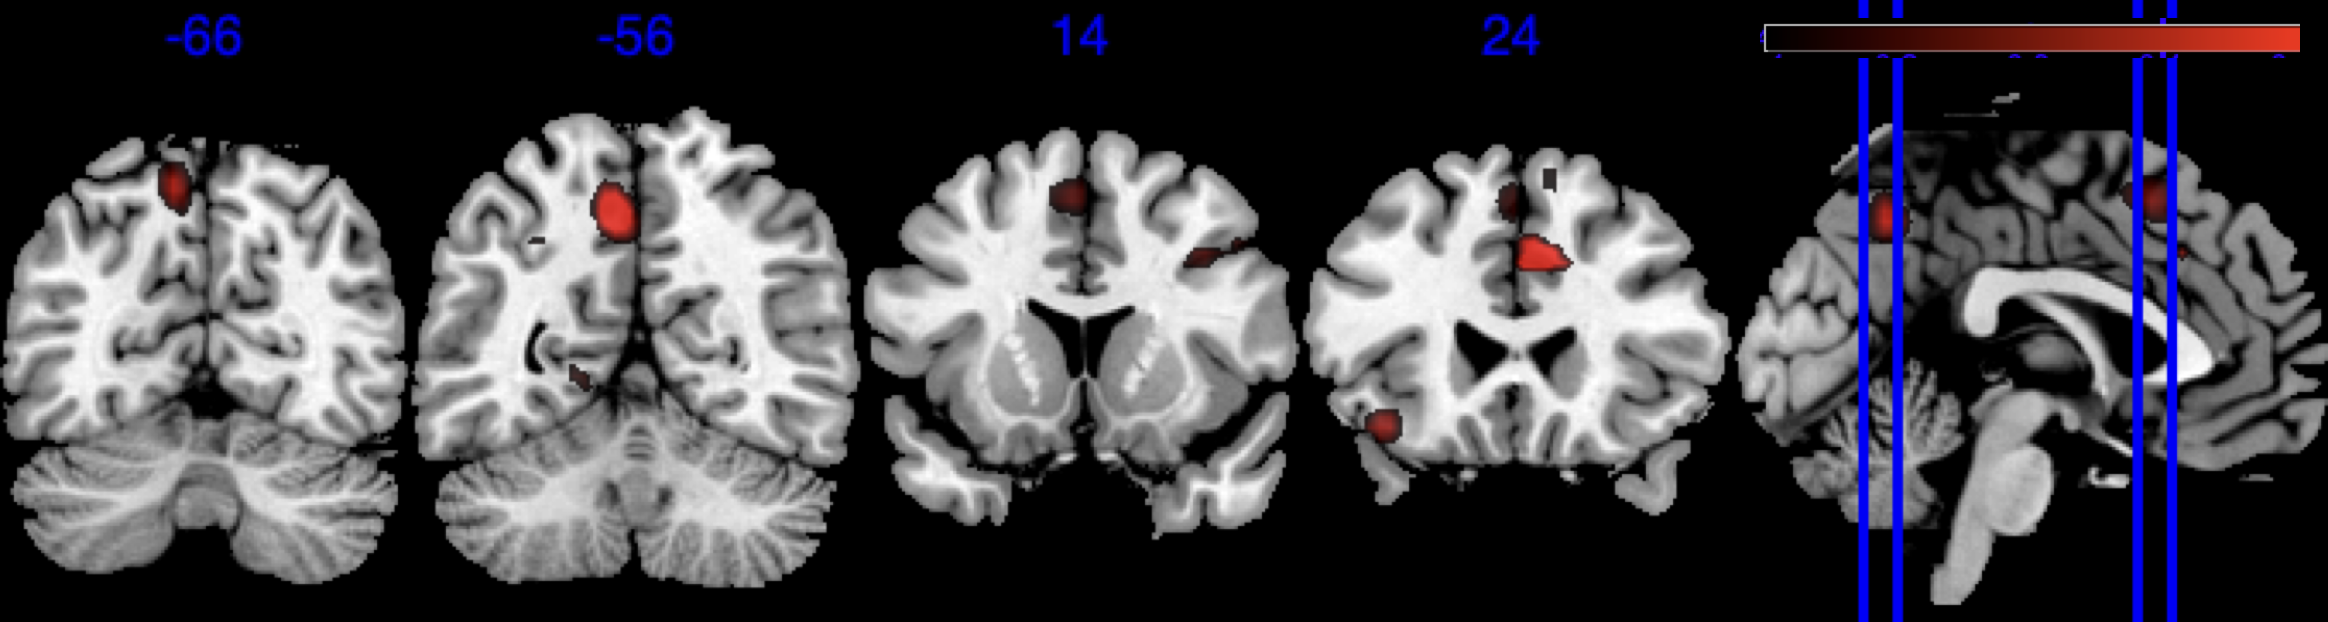

We performed 100,000 iterations for the outcome model (1), discarding the first 50% as burn-in and thinning to retain 1,000 posterior samples. For the mediator model (2), we ran 40,000 iterations with a 30,000 burn-in, thinning every 10 iterations to obtain 1,000 posterior samples. Table 3 gives a summary of both the overall NIE and NDE and the top seven regions identified with the largest number of active voxels. The definition of NIE in each region is , where is the collection of all voxels in region . The rule for selecting the active voxels is based on cutting the posterior inclusion probability (PIP) at 50%, and the three regions with active voxels are reported in Table 3. Due to the very small effect sizes and low signal-to-noise ratio, we also include regions with voxels’ PIP greater than 10%. The posterior of NDE has a mean of 0.27 with the 95% credible interval . The posterior of NIE has a mean of 0.0885 with the 95% credible interval . The total effect of parental education level on general cognitive ability score is 0.36, with 95% credible interval (0.29,0.45). This suggests that parents with college degrees have a positive impact on children’s cognitive abilities, and about 25% of the effect is mediated through brain cognitive development. Figure 5 shows the estimated activation regions and the NIE in coronal view slides. Among the top identified activation regions, the most interesting is the left precuneus, which plays a key role in episodic memory, visuospatial processing, and self-consciousness (lou2004parietal; wallentin2006parallel). This region has been consistently implicated in cognitive processes related to memory retrieval and spatial awareness, which are crucial components of children’s cognitive development. In addition, other identified regions, such as the left inferior parietal region and the left postcentral gyrus, are associated with the interpretation of sensory information (radua2010neural; diguiseppi2023neuroanatomy). These regions are involved in integrating and processing sensory inputs, which are essential for tasks that require coordination between perception and cognition, such as working memory and executive function. These findings align with existing literature on the neural correlates of cognitive function, particularly in children. By identifying regions that have been consistently associated with cognitive processes, our results not only demonstrate the scientific validity of the BIMA approach but also provide meaningful insights into the brain areas that underlie cognitive abilities as captured by the ABCD study.

| Positive posterior mean of the spatial mediation effects (color range ) |

![]() |